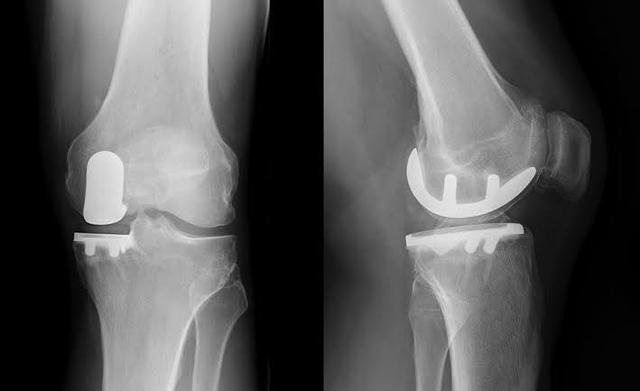

● Si les symptômes de l'articulation sont particulièrement sévères et que le patient a développé une...Déformations articulaires évidentesSi vous êtes incapable de marcher normalement, si vous ressentez des douleurs articulaires importantes lorsque vous marchez plus de 500 mètres et si vous êtes gravement affecté par des douleurs au repos ou pendant votre sommeil, il y a une indication pour une prothèse articulaire.L'arthroplastie du genou peut être le seul moyen d'aider complètement le patient.。

9. remplacement du genou :Si l'arthrose a entraîné une déformation évidente de l'articulation, qui affecte gravement le traitement de la vie du patient, le moment est venu de résoudre complètement le problème du patient par la mise en place d'une prothèse de genou.

Apparition tardive : articulations artificielles pour soulager la douleur sévère

Aux stades avancés de la maladie, le cartilage du patient est presque usé. Sans l'amortissement du cartilage, les os frottent directement l'un contre l'autre. À ce stade, les seules options sont de remplacer l'articulation par une prothèse ou de procéder à une arthrodèse, qui est rarement utilisée car elle peut affecter gravement la mobilité du patient après l'opération.